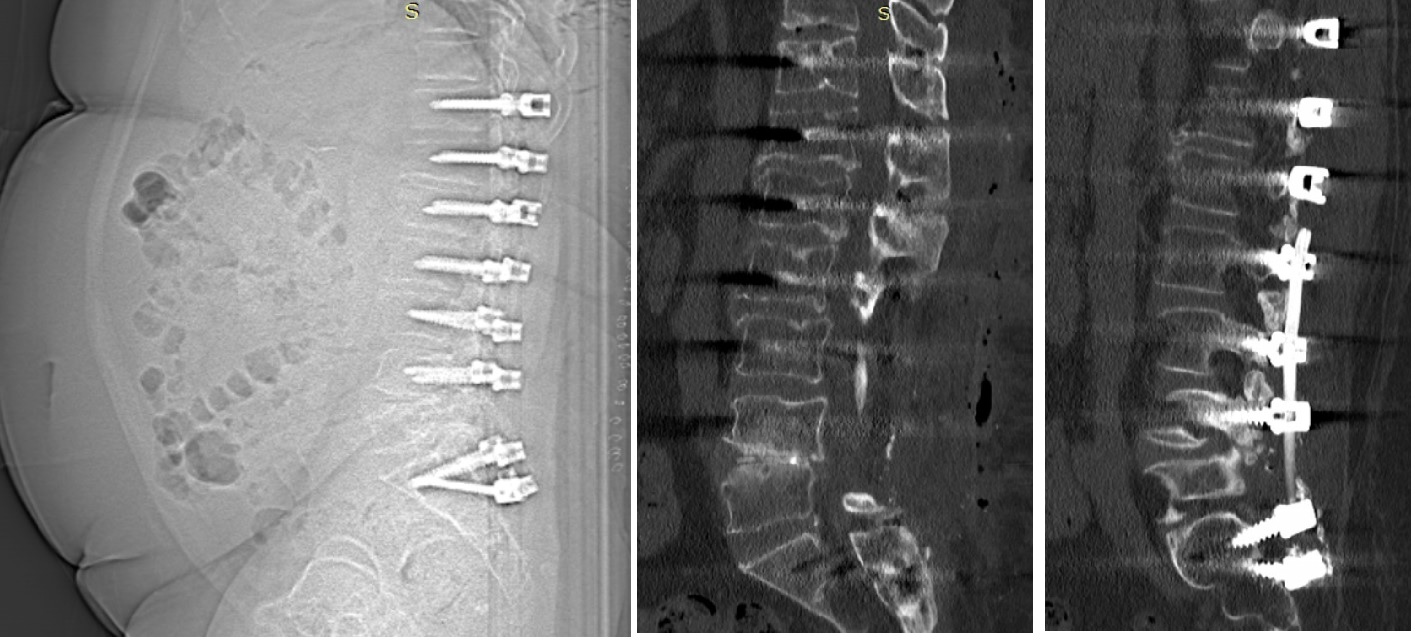

Hastanın beraberinde getirdiği ve bir önceki yıla ait lomber MRG incelemesi aşağıdadır.

2021 Yılı MRG İncelemesi - Lomber Enstrüman Gevşemesi

Resim 1: Bir yıl önce yapılmış olan MRG incelemesinde T11-L5 seviyelerinin stabilize edilmiş olduğu, L2-L4 seviyelerinde laminektomi bulunduğu ve L4-5 seviyesinde kanalda darlık olduğu görüldü. Ayrıca lomber lordozun düzleşmiş olduğu dikkati çekmektedir. MRG kalitesi düşüktür.

Uzun segment (T11-L5) stabilizasyon yapılmış olan hastanın istirahatte bulunan kalça ve bacak ağrıları ve uyuşma yakınmaları spinal kanalda ya da nöral foramenlerde daralmalara bağlı nöral bası düşündürtmektedir (Bacaklardaki kramplar nörojenik kladikasyon tablosunun bir parçası olabilmekle birlikte, tipik siyatalji tablosunun bir parçası değildir, başka sebepler de aramak gerekir).

Hareketle artan bel ağrısı instabilite, alt lomberde implant üzerine basmakla uyandırılan şiddetli ağrı ise implant gevşemesi lehinedir.

Bu hastada olası tanılar komşu segment hastalığı (T11 üstü ve L5 altı seviyelerde hızlanmış dejenerasyona bağlı darlıklar ve/veya instabilite) ve implant gevşemesidir. Stabilize edilmiş L4-5 seviyesinde darlık görülmesi, buna karşın L5-S1 seviyesinin nisbeten korunmuş oluşu L4-5 seviyesinde füzyon oluşmadığı ve implant gevşemesi olabileceği yönünde fikir oluşturmaktadır.